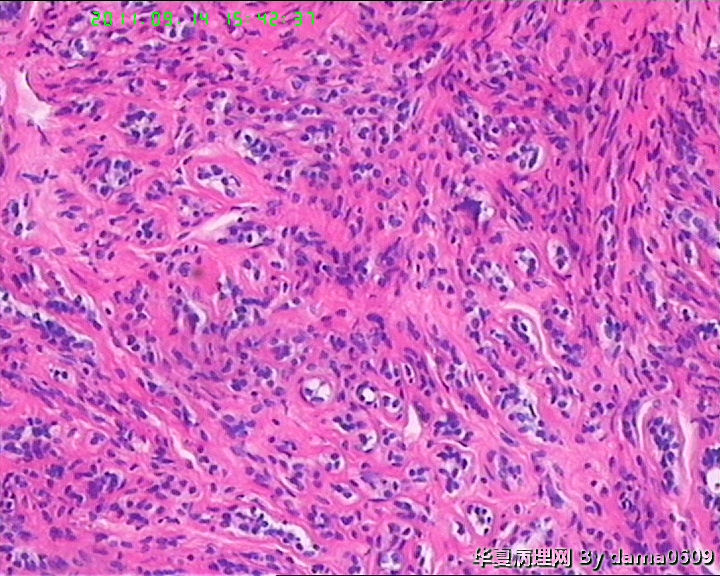

女,22岁,乳腺肿物,病史不详。

不整形软组织肿物一个,V:2.0x1.5x1.5cm。无包膜。切面实性,灰白色,小结节状,质中。

镜下结构复杂,图3、4、8、10、11、12、13、15、17、18、19、20为肿物中央区域,占标本大部分,图1、2、7、14为肿物边缘部分,图5、6、9、16、21为二者交界处。有点乱,不好意思,请老师别介意。

请教老师,诊断:硬化性腺病,可以吗??谢谢!!

• 乳腺肿物,急于求教!!图3

图3

会诊结果::(乳腺)腺管腺病,伴纤维腺瘤形成。

该例患者经上级医院会诊,回报:(乳腺)腺管腺病,伴纤维腺瘤形成。